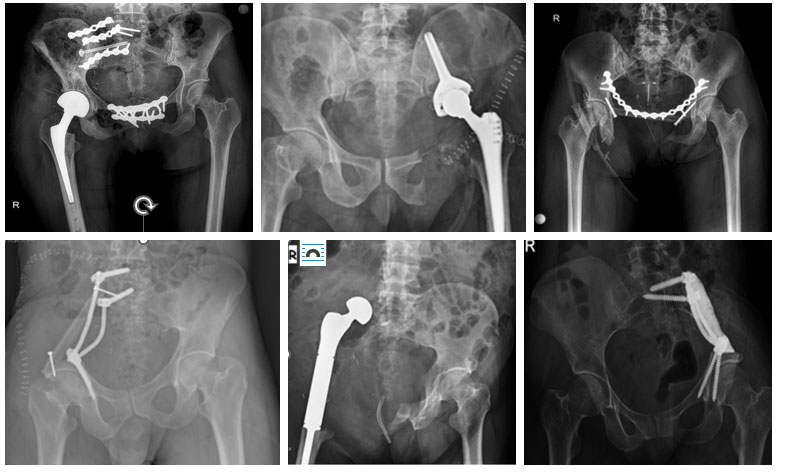

Все типы рака могут метастазировать в таз и вертлужную впадину, которая является вторым по распространенности местом метастазирования после позвоночника. Хирургическое лечение большинства костных метастазов в таз и вертлужную впадину состоит из удаления опухоли (Абразия), заполнения полости (костный цемент) и, у пациентов, которым это необходимо, фиксации (пластины-винты) и укрепления. В случаях, когда этот метод не работает или считается недостаточным, мы проводим резекцию (гемипельвэктомию) и реконструкцию у соответствующих пациентов.

Хирургическое лечение костных сарком (остеосаркомы, саркомы Юинга и хондросаркомы), расположенных в тазу и вертлужной впадине, заключается в чистой резекции опухоли с широкими краями. Из-за анатомического расположения эта хирургическая процедура называется гемипельвэктомией. Гемипельвэктомия - самая ответственная и сложная операция в ортопедической онкологии, требующая серьезного опыта и тщательного планирования.

Существует два основных типа гемипельвэктомии: внутренняя и внешняя. При внутренней гемипельвэктомии сохраняется одна сторона ноги, а при внешней гемипельвэктомии опухоль удаляется вместе с ногой.

Мы часто выполняем внутреннюю гемипельвэктомию при саркоме, расположенной в тазу - вертлужной впадине. Однако внешняя гемипельвэктомия может быть выполнена в случае рецидива, когда невозможно сохранить 2 из 3 основных структур (тазобедренный сустав, седалищный и бедренный нервы), когда невозможно сохранить и реконструировать основные сосуды (наружные подвздошные и бедренные артерии), когда невозможно обеспечить покрытие мягких тканей, а также при наличии неконтролируемой инфекции.

Внутренняя гемипельвэктомия обычно подразумевает удаление всей или части одной половины опухолевой тазовой кости и классифицируется в зависимости от удаляемой области. Существует 4 основных типа.

Тип 1: резекция подвздошной кости. Это относительно простая и низкорискованная резекция. Образовавшаяся полость часто реконструируется с помощью стержней и винтов и/или малоберцовой кости, костного цемента, реконструкции и фиксации. Оставлять ее пустой после реконструкции - тоже вариант, но мы редко используем этот метод.

Тип 2: Резекция вертлужной впадины или тазобедренного сустава. Это относительно более сложный и потенциально инвалидизирующий тип резекции. Существует повышенный риск повреждения крупных сосудов (наружной подвздошной артерии) и нервов (седалищного и бедренного). Пространство, оставшееся после резекции, часто реконструируется с помощью протеза (Icecream, Lumic и т.д.). Замена тазобедренного сустава с сохранением - еще один вариант. В зависимости от размера опухоли может быть выполнена комбинированная резекция 1 и/или 3 типа.

Тип 3: резекция лобковой кости. Это особая операция из-за близости внутренних органов (мочевой пузырь, уретра и т.д.) и магистральных сосудов (бедренная артерия - вена), а также мышц (подколенное сухожилие, Большая приводящая мышца и т.д.) и связок (крестцовый бугор). Послеоперационная полость часто закрывается проленовой сеткой для предотвращения развития грыжи. При двусторонней резекции может быть использована реконструкция с помощью малоберцовой кости и пластины.

Тип 4: К нему прибегают, когда крестец включен в процесс. Он часто выполняется вместе с резекцией первого типа и называется резекцией крестцово-подвздошного сочленения. Если край резекции располагается ближе к внутренней стороне, может развиться повреждение нерва, называемого крестцовым корешком, и, хотя это случается редко, могут пострадать мочеиспускание, кал и сексуальные функции.

В некоторых случаях нам приходится комбинировать эти виды резекции. Например, тип I+II, тип I+IV, тип II+III.

Реконструкция полости после внутренней гемипельвэктомии может быть выполнена с помощью множества различных методов. Наиболее распространенными методами реконструкции являются протезирование опухоли (транспозиция бедра, мороженое/люминесцентный протез и т.д.), Малоберцовая кость и/или спасение (жидкий азот или лучевая терапия), но также возможен вариант оставления полости пустой без реконструкции. Тип резекции, оставшийся костный запас и общее состояние пациента особенно важны при определении типа реконструкции.